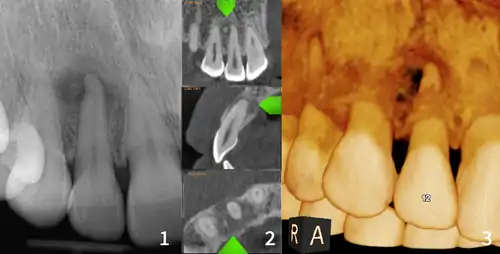

xray and CBCT scans of periapical cemental dysplasia